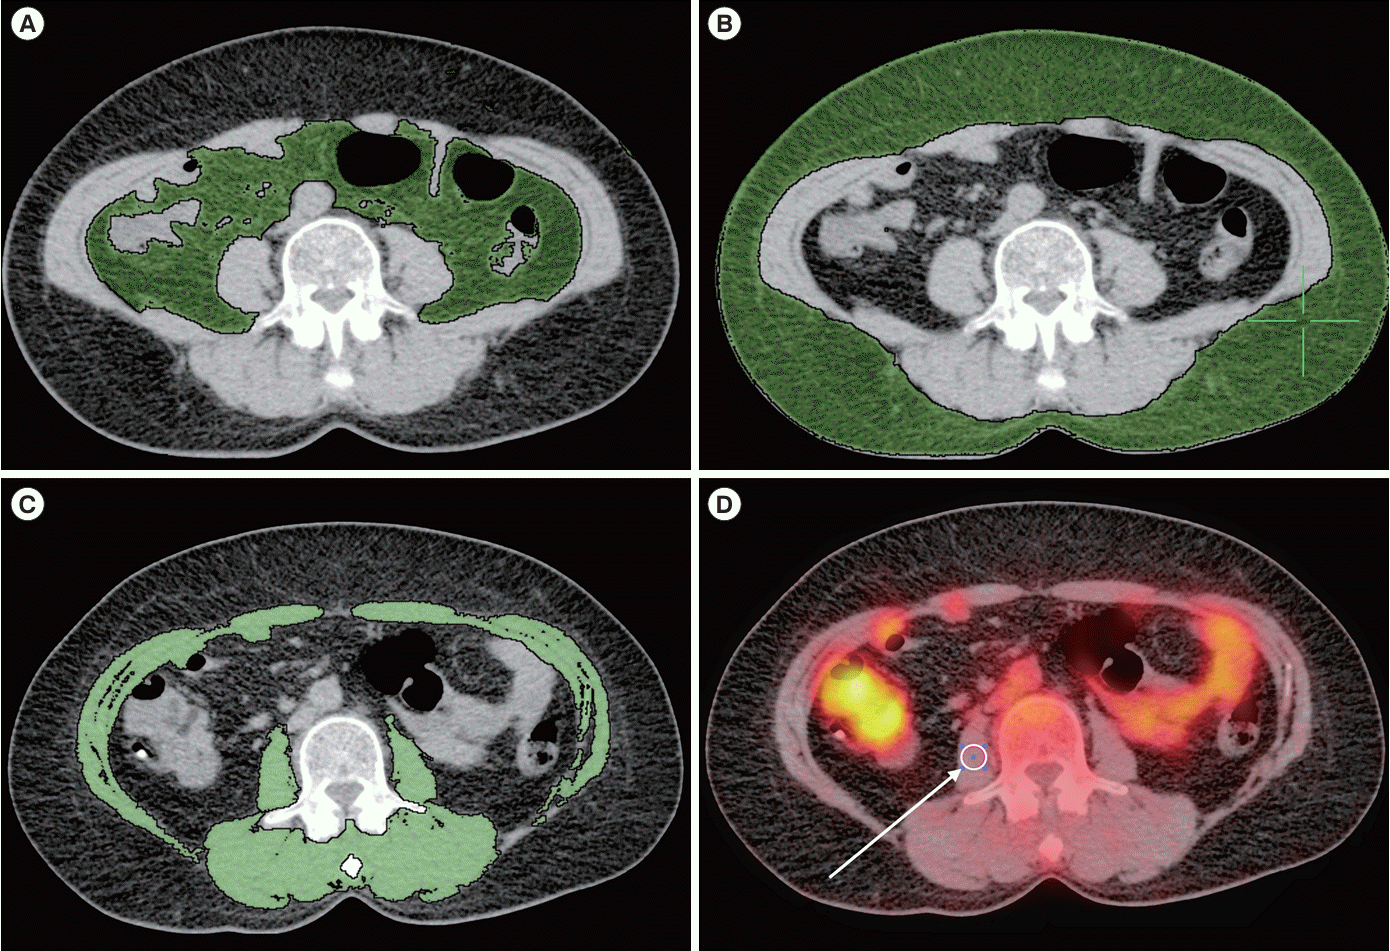

For each patient, the amount and distribution of abdominal fat was measured using an axial image showing the transverse process of the fourth lumbar vertebra (L4) as a landmark. Fat tissue falling within the predefined HU range for adipose tissue [13] was identified. VAT was defined as fat located within the visceral cavity. SAT was defined as fat located outside the visceral cavity, excluding any fat located within the muscular fascia or cutaneous tissue (Fig. 1). WC was measured by outlining an ROI along the cutaneous area at the level of the umbilicus.

Cross-sectional muscle area (CSMA) was measured using an axial image showing the transverse processes of the third lumbar vertebra (L3) as a landmark. The image included the psoas, paraspinal, transverse abdominis, external oblique, internal oblique, and rectus abdominis muscles (Fig. 1C). CSMA (in cm2) within the specified HU range for muscle tissue [14,15] was identified. The mean HU value within the ROI was also calculated. In addition, a circular ROI with a 1 cm diameter was positioned within the psoas muscle to assess glucose metabolism (Fig. 1D) [16]. To validate the parameter, CSMA was compared with the standardized skeletal muscle index (SMI) obtained by bioelectrical impedance analysis (BIA).

Fig. 1.

Measurement of body composition parameters. (A) Abdominal visceral adipose tissue and (B) abdominal subcutaneous adipose tissue show in an axial image using the transverse process of the fourth lumbar vertebra. (C) Cross-sectional muscle area and (D) circular region-of-interest with a 1 cm diameter within the psoas muscle (white arrow) shown in an axial image using the transverse processes of the third lumbar vertebra.